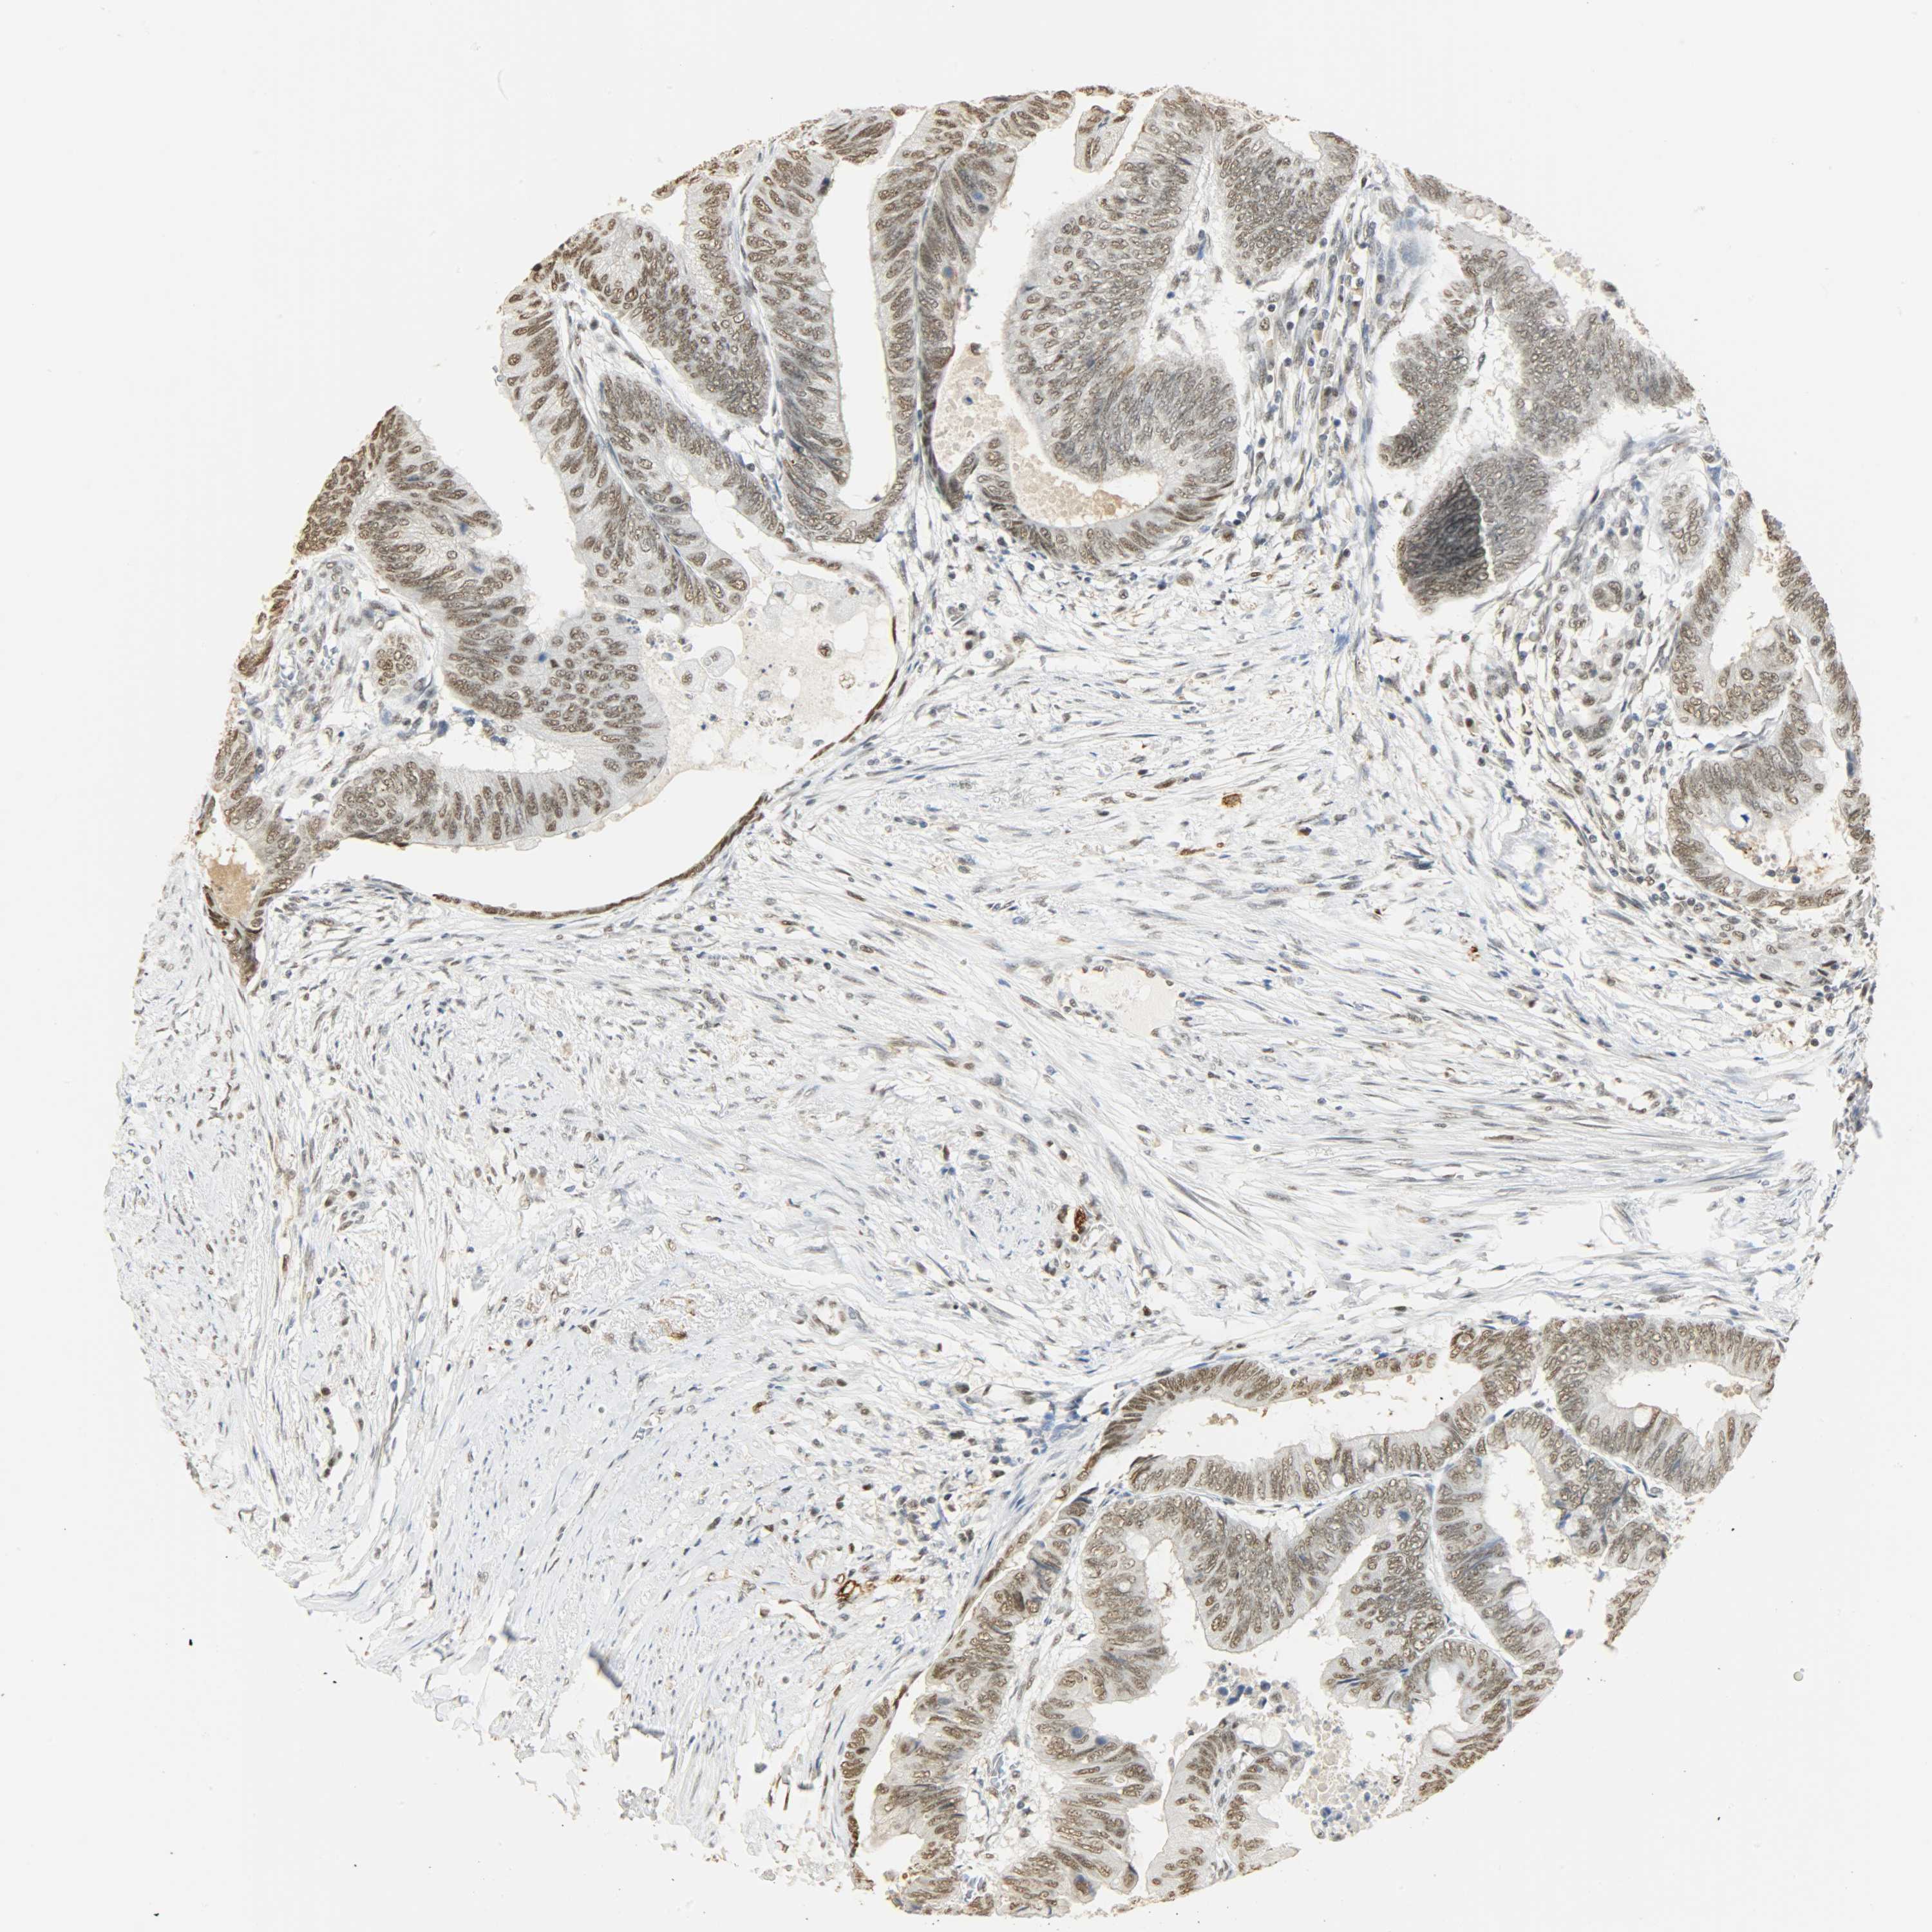

CANCER COLORECTAL CANCER Show tissue menu

Colorectal cancer

Human cancer

Colon adenocarcinoma

Rectum adenocarcinoma